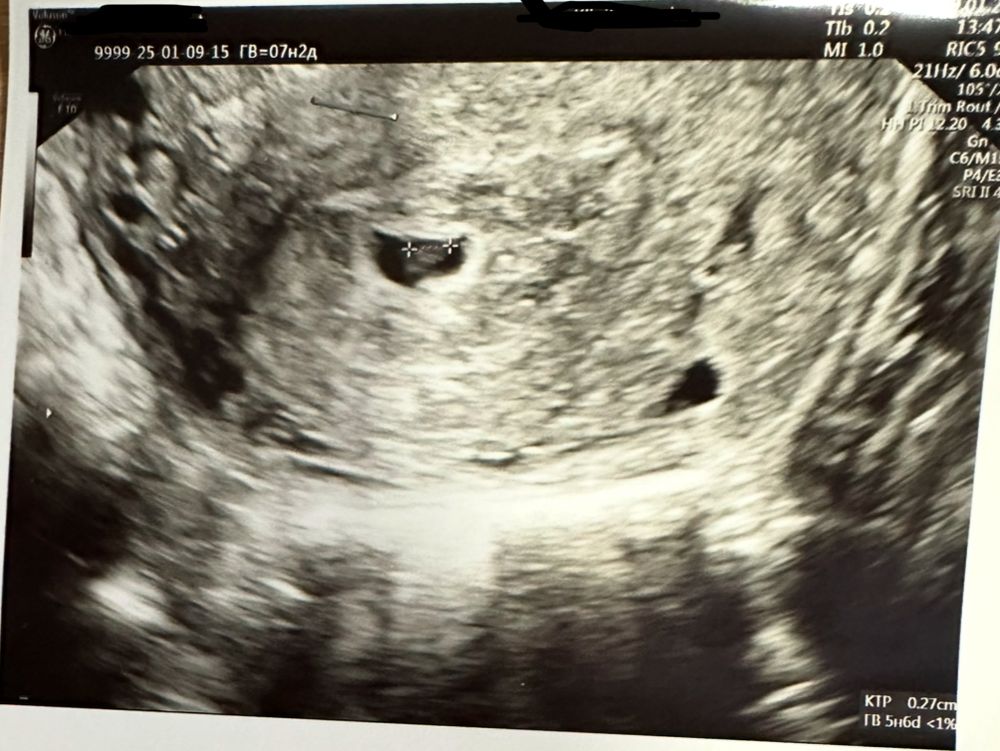

30.12.24. Сходила на узи.

пя 3мм

9.01.25г. Еще раз сходила на узи:

ПЯ 8.5мм

КТР эмбриона 2,7 мм(под вопросом?)

ЧСС(-)

ЖМ-4мм

как по мне, плохо растет пя

Один врач сказал, что скорее всего замершая. Второй сказал, что срок еще мал из-за поздней овуляции. Почему тогда такой большой жм.

Лёвушка, думаю, действительно только контроль узи. На фото замерян ЖМ как я понимаю… рядом и правда что-то похожее на эмбрион, но не четко.